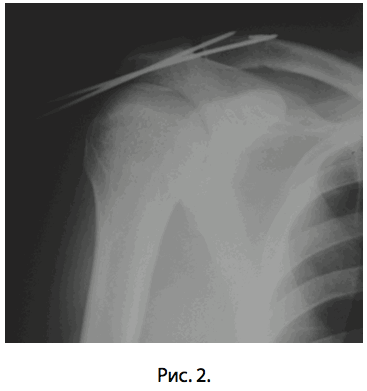

На восьмые сутки с момента травмы пациенту выполнена операция: открытое вправление вывиха правой ключицы и фиксация правого акромиально-ключичного сустава малоинвазивной «пуговичной» системой и 2-мя спицами трансартикулярно под контролем эОП (рис. 2). В ходе операции из доступа около 3-х см выполнен полноценный дебридмент околосуставной области, а также удаление рубцовых интерпонентов из полости акромиально-ключичного сустава.